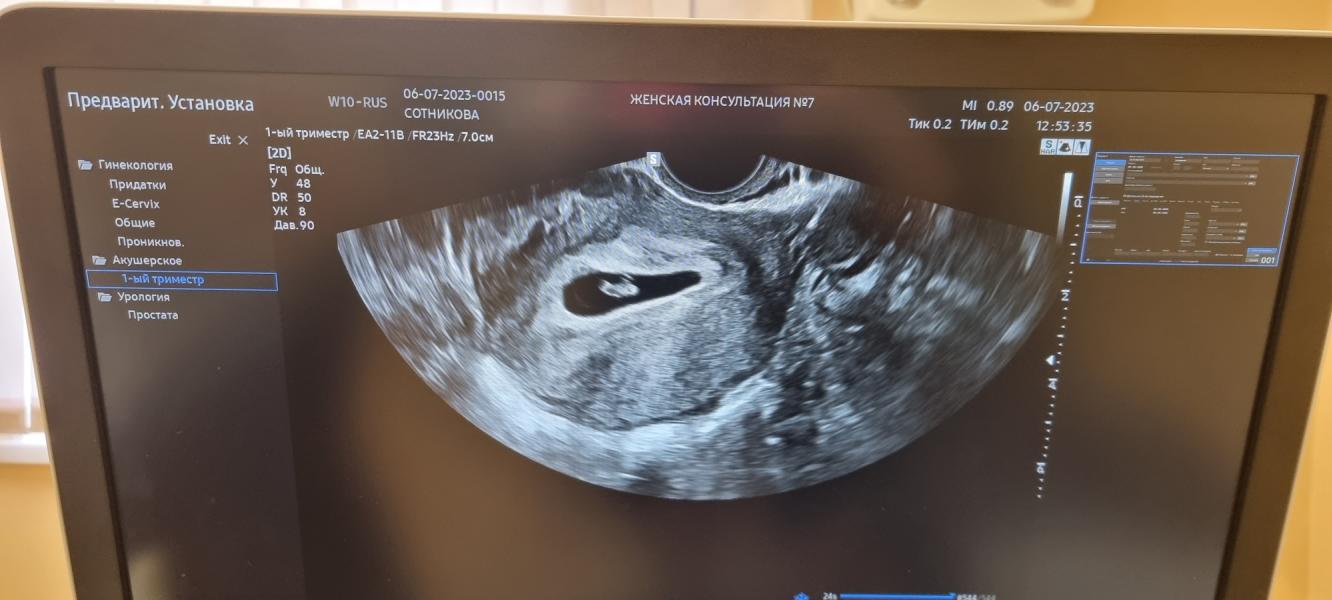

3 фото: наше первое фото, уже месяц почти прошёл. А в понедельник мы идем делать новое фото и первый скрининг.